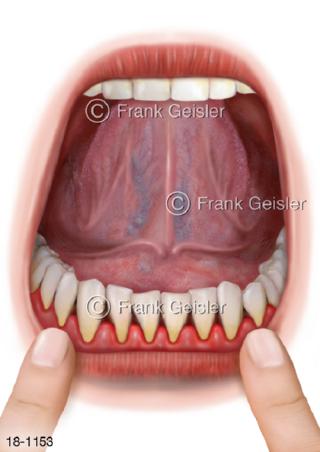

18-1153 Parodontose. Entzündung Zahnfleisch